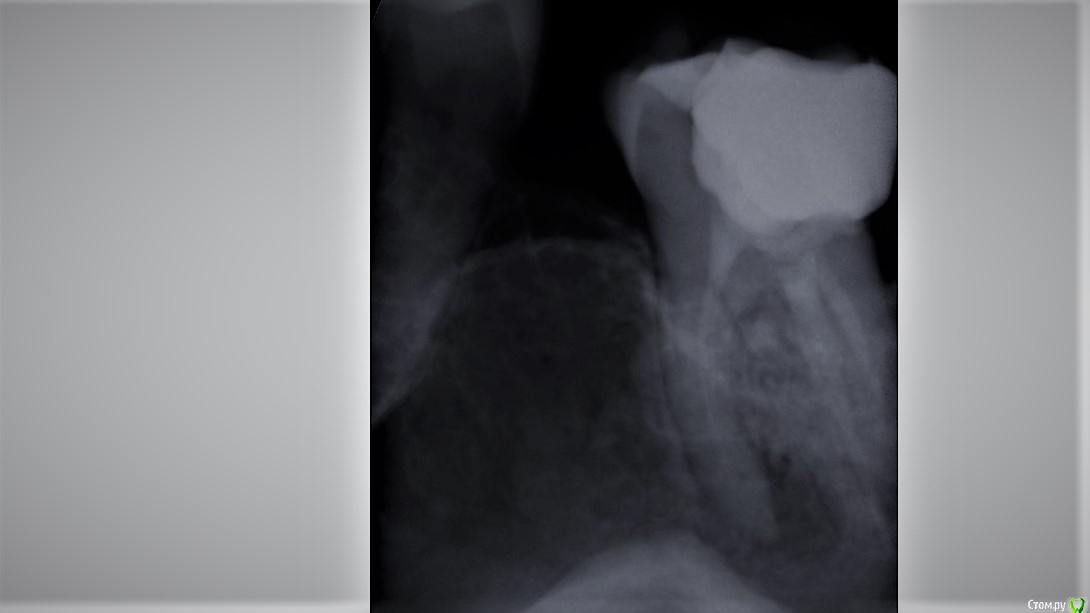

Wedernikoff Опубликовано 5 октября, 2017 Автор Поделиться Опубликовано 5 октября, 2017 Доброе утро. Вопрос возник потому, что мне врачи сказали, что там "огромная кистогранулёма" (это цитата). И зуб можно попробовать спасти только у очень опытного микроскописта без гарантии. Не болит, начала потихоньку крошиться пломба. Спасибо Вам за отклик. Отличного дня Ссылка на комментарий

Wedernikoff Опубликовано 5 октября, 2017 Автор Поделиться Опубликовано 5 октября, 2017 Быть может, по этому снимку будет видно нормально. Ссылка на комментарий

St. Опубликовано 5 октября, 2017 Поделиться Опубликовано 5 октября, 2017 Да, воспаление на корнях действительно присутствует. Метод лечения это перелечивание каналов, на которое и правда не может быть гарантии в принципе. После перелечивания нужно накрыть зуб коронкой Ссылка на комментарий